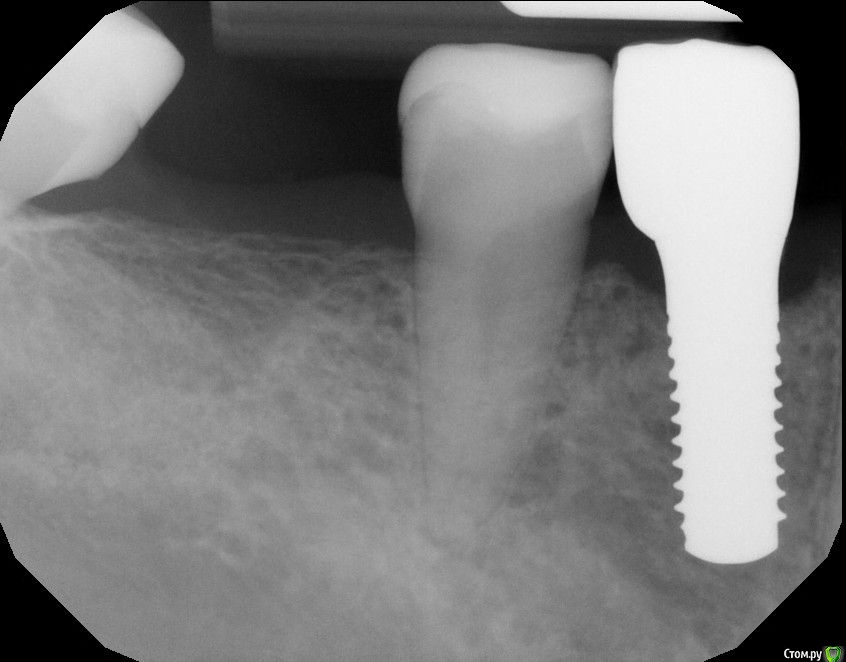

Astronaft Опубликовано 25 января, 2021 Автор Поделиться Опубликовано 25 января, 2021 Спасибо.День операции, 12 недель, день цементировки. 3 1 Ссылка на комментарий

Astronaft Опубликовано 24 января, 2021 Поделиться Опубликовано 24 января, 2021 (изменено) Одиночный цирнокиевый имплантат и расщепление без графта. Пациентка:тонкая хрупкая женщина 55 лет, сконцентрированная на своем здоровье, в некоторой мере мнительная.всегда тяжелые заживления после удалений (по опросам)есть результаты Клиффорд теста (такая книжка под 200 страниц с in vitro аллерго-пробами на все известные материалы) Поставленная цель:только цирконий Мне было интересно найти вариант найболее приемленый пациентке и мне. С минимом хирургического риска и риском сожаления пациентки про выбор костного материала. Во-первых, я не использую аллографты - философски, чужие протеины, неприятный запах - просто основываясь на своем мнении.Во-вторых, мнительные пациенты склонны "пойти и почитать" до или потом и как следствие внушить себе вещи которых может и не было. Но по скольку мысль материальна... Все обсудил заранее.План: ридж сплит (расщепление), имплантат без графта, свободный СТ графт; если случается вестибулярная рецессия - пилим зирконий во рту. Ридж сплит сделан пьезотомом - крестальный и вертикальные пропилы на глубины около 8-10мм.Пилотное сверло.Развдвинул кость остеотомами от 1.6мм до 3.5мм в диаметре.Очень мягкая кость - напомнила мегкую максиллу плотности ногтевой пластинки вестибулярно.Имплант встал легко, но торк 40нсм. СТ графт из области 18. Деэпителизирую скальпелем уже потом. Тут интересно отметить, что я перестал боятся ошметков эпителия.Пончо сверху имплантата (а-ля шашлык Карлоса).Швы. PTFE всегда хорош. 12 недель.Красивая десна.Периотест -5.8 - отличный результат.Оттиск. Циркониевая коронка симметричная другой стороне. Изменено 24 января, 2021 пользователем Astronaft 19 Ссылка на комментарий